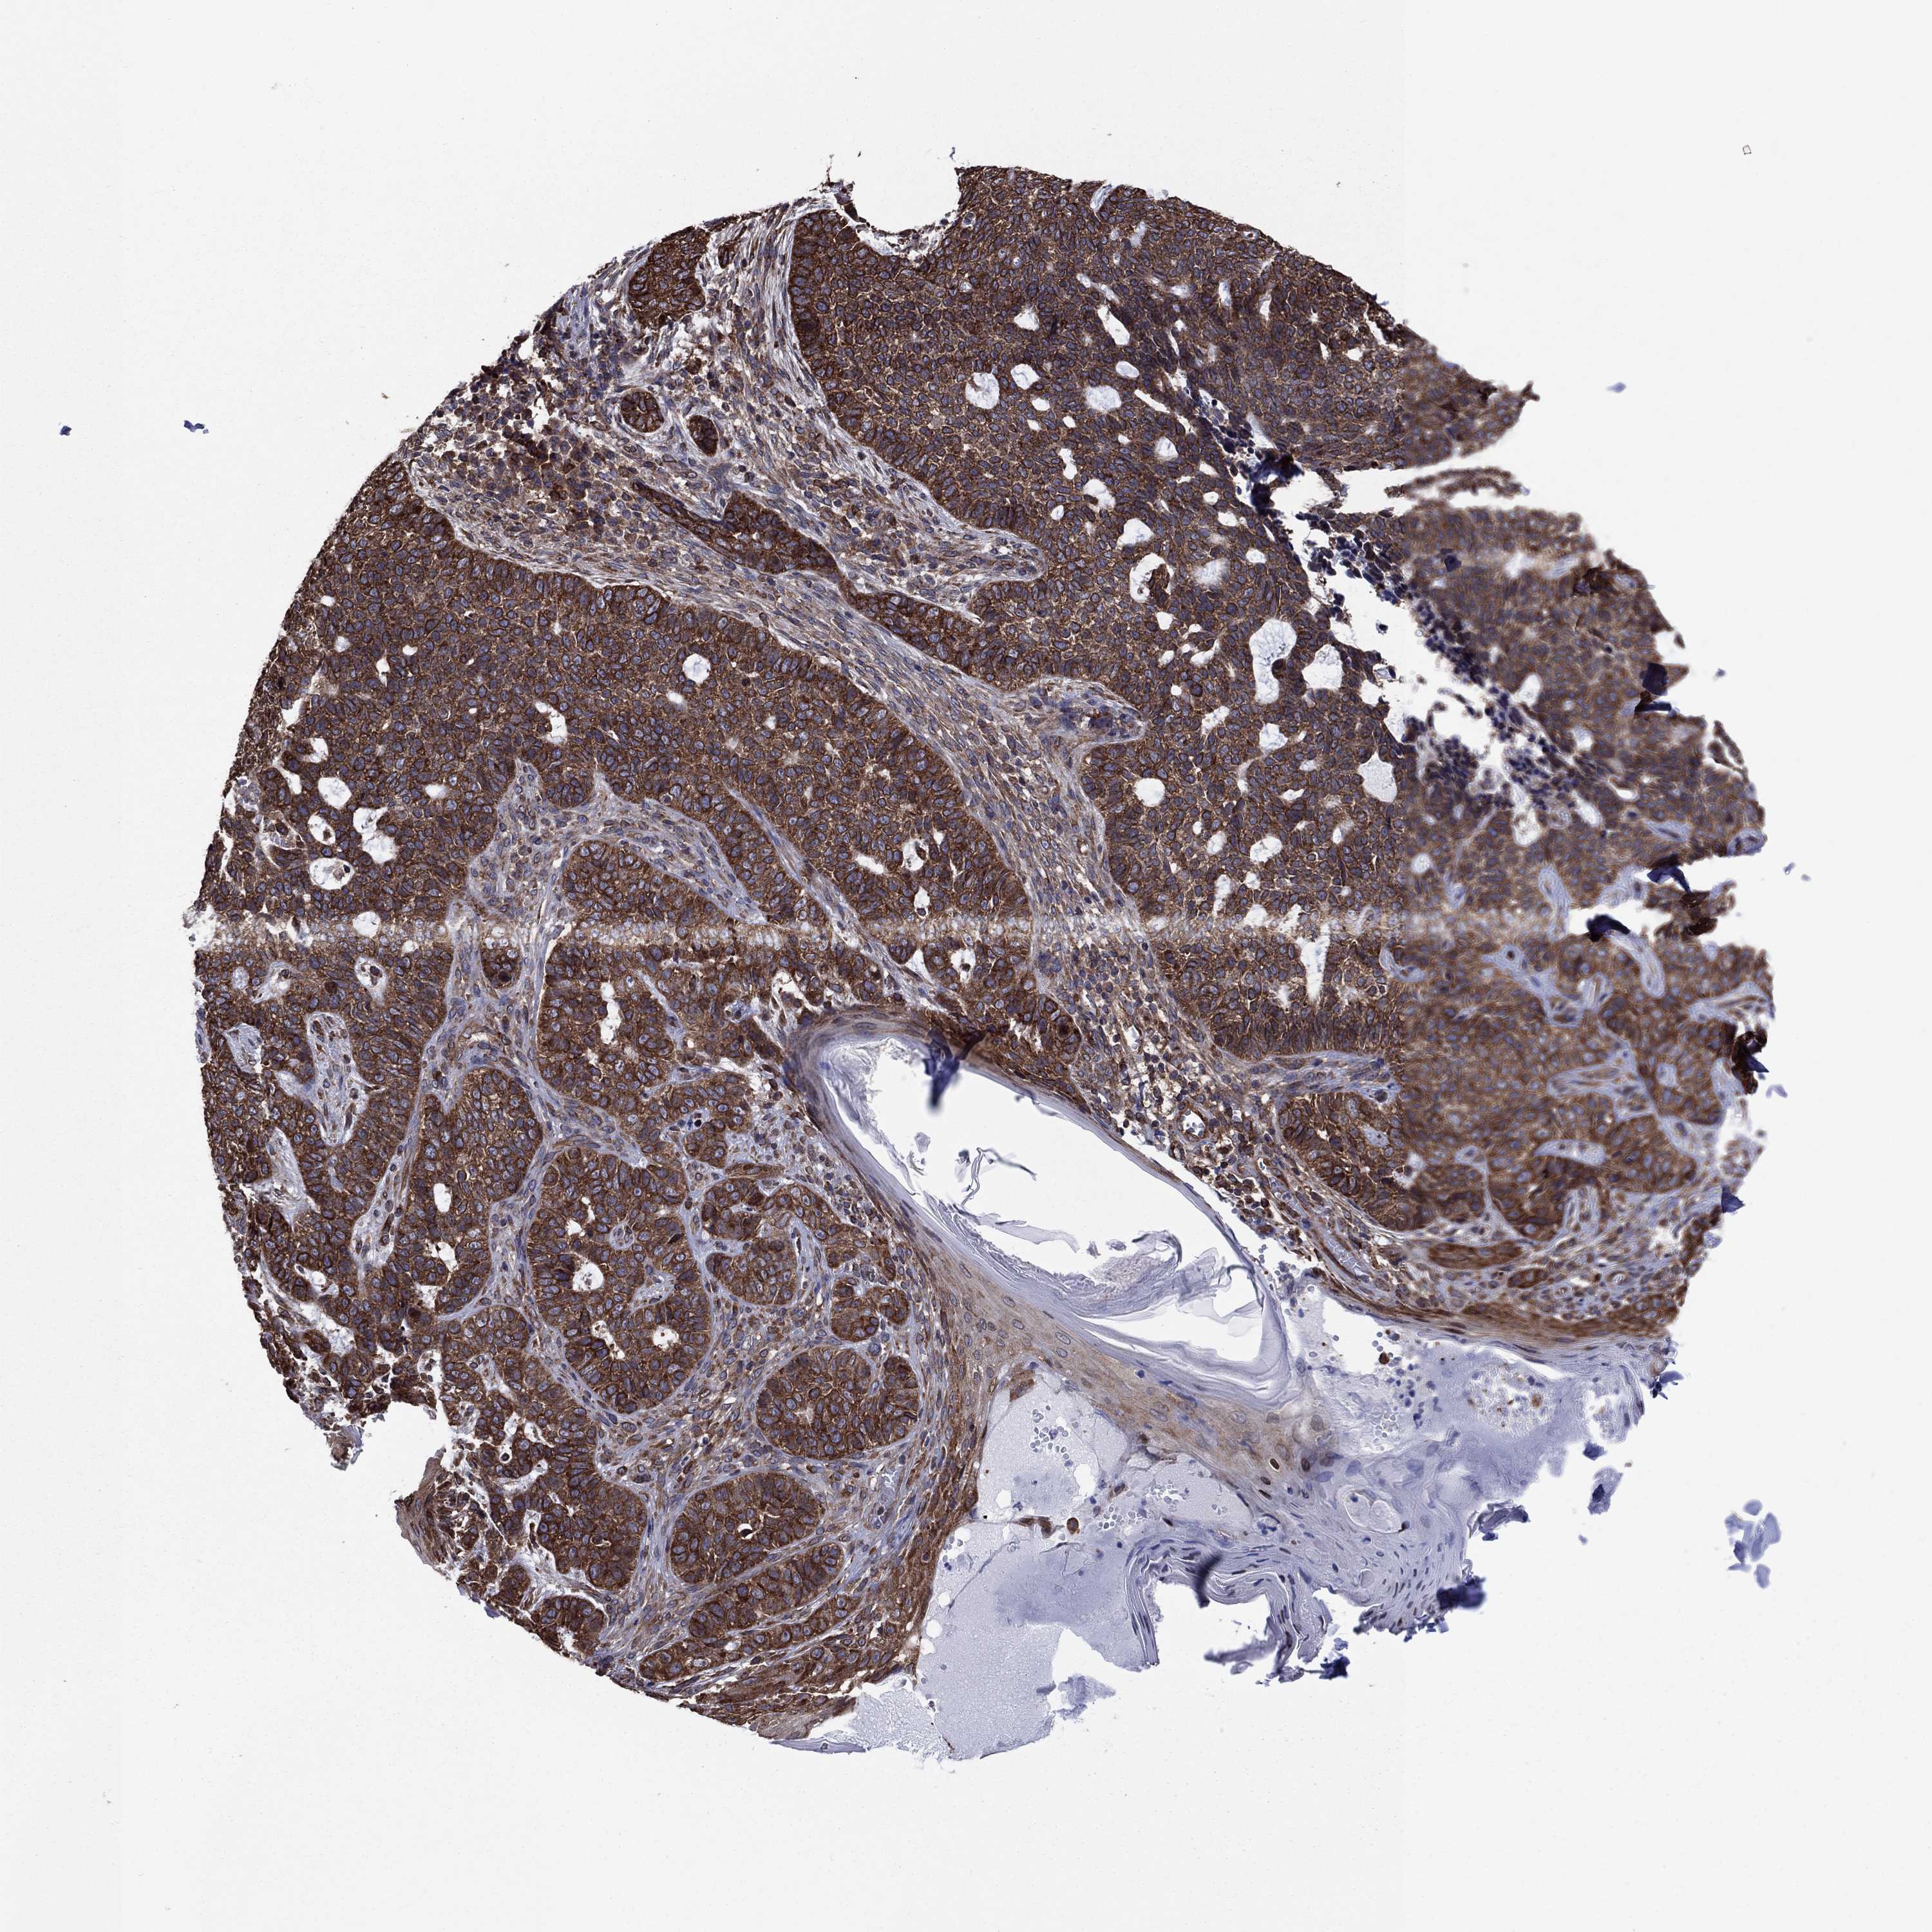

Basal cell and squamous cell cancer

SKIN CANCER - Protein expressioni

A mouse-over function shows sample information and annotation data. Click on an image to view it in a full screen mode. Samples can be filtered based on level of antibody staining by selecting one or several of the following categories: high, medium, low and not detected. The assay and annotation is described here.

Antibody stainingi

Antibody staining in the annotated cell types in the current human tissue is reported as not detected, low, medium, or high, based on conventional immunohistochemistry profiling in selected tissues. This score is based on the combination of the staining intensity and fraction of stained cells.

Each image is clickable and will lead to virtual microscopy that enables deeper exploration of all samples and also displays staining intensity scores, fraction scores and subcellular localization as well as patient and tissue information for each sample.

Antibody HPA040304

Staining

High

Medium

Low

Not detected

Intensity

Strong

Moderate

Weak

Negative

Quantity

>75%

75%-25%

<25%

None

Location

Nuclear

Cytoplasmic/membranous

Cytoplasmic/membranous,nuclear

Basal cell carcinoma